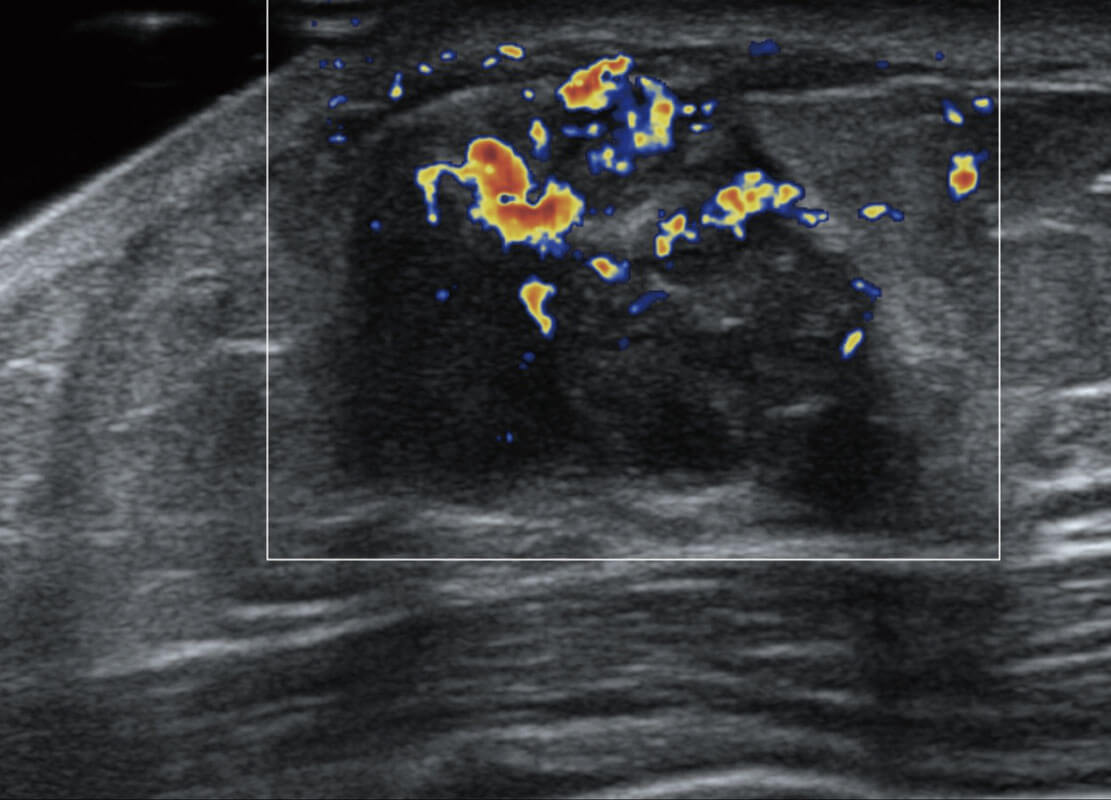

生殖健康

P60优异的图像质量搭载专科探头,在妇科基础疾病的诊断、卵泡生长的监测、输卵管通畅情况的判别等方面为您提供生殖应用方案。

• 腔内妇科-宫腔分离

• 腔内妇科-卵巢

• 腔内三维-宫内节育器

• 腔内三维-光影成像